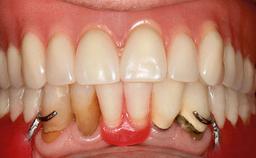

Mandibular Overdenture Supported by a CAD/CAM-milled Bar with Long Distal Extensions on Two Conventionally Loaded Implants

Defining Characteristics Fully edentulous lower jaw to be rehabilitated with an implant-borne removable overdenture